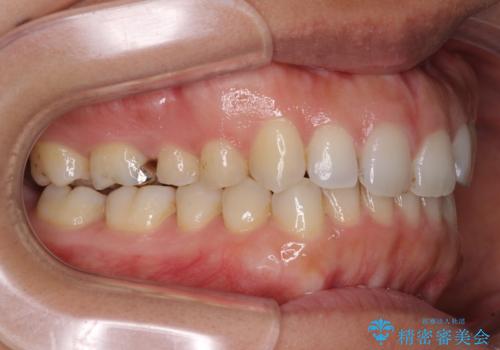

受け口傾向の前歯 すきっ歯の改善

- 前歯の隙間と口元の突出感を気にして来院された患者様です。

嚥下時に舌を突出させる癖があり、成長期に下顎が有意に成長し、歯と歯の間に隙間ができてしまいました。

舌の癖を改善し、インビザラインにて治療を行うこととしました。

舌癖を改善したことで、隙間や突出感を改善することができました。

隙間は後戻りしやすいため、舌側を細いワイヤーで固定することとしました。